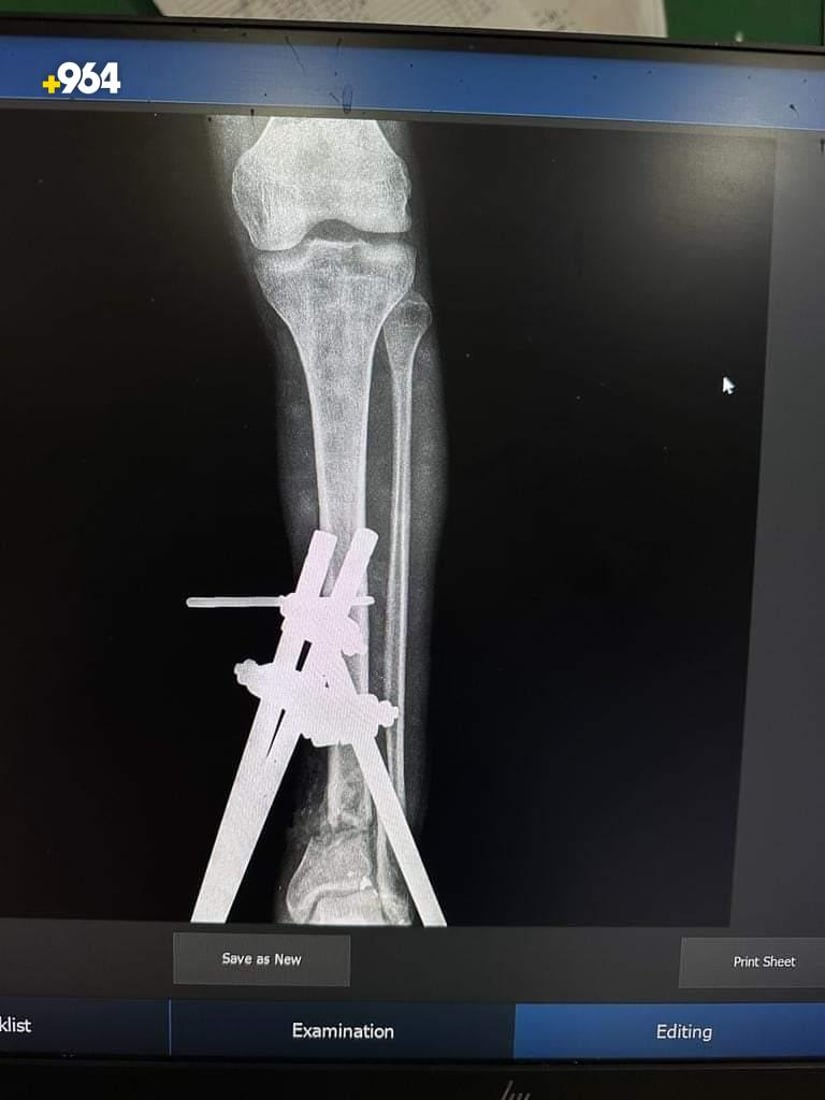

صور: أطباء ينجحون في تثبيت كسر مضاعف أسفل الساق لمصاب في تلعفر

نجح فريق طبي في مستشفى بلدة تلعفر العام بنينوى، اليوم الاثنين، من تثبيت كسر أسفل عظم الساق لشاب، بعد عملية جراحية نادرة، وفقاً لإدارة المستشفى.

تمكّن فريق طبي متخصص في قسم جراحة العظام والكسور بمستشفانا من إجراء عملية معقدة لشاب في السابعة عشرة من العمر، كان يعاني من كسر في الساق.

الفريق الذي ترأسه الدكتور زكريا ربيع، اكتشف نتيجة الفحوصات أن الشاب يعاني من كسر مضاعف أسفل عظم الساق الأيسر، إلى جانب جرح تهتكي وفقدان في الانسجة الرخوة.

الفريق نجح في تثبيت الكسر بالمثبت الخارجي بعد إجراء الإسعافات الأولية.